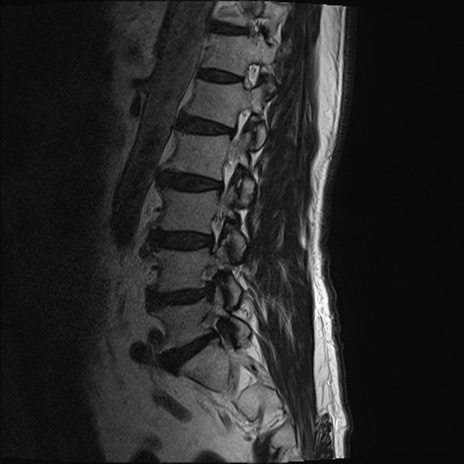

【整形】TIPS症例2 腰椎MRI T2WI(矢状断像)

【症例】70歳代男性

【主訴】左下肢痛

【現病歴】2週間前くらいから腰痛、左下肢痛あり。左臀部から大腿、下腿外側のしびれが常時ある。歩行とともに同部位の痛みあり。

【身体所見】Lasegue70-/60+、Bragard-/±、PTR ±/±、ATR -/-、IP 5/5、TA 5/4、TS 5/5、EHL 右第1足趾なし/3、FHL 5/5、hypersthesia(-)、足背動脈触知良好

異常所見と診断は?